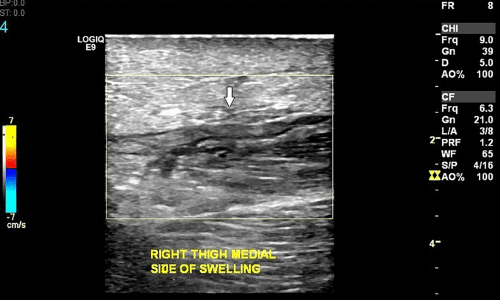

Filarial Dance Sign Ultrasound

Filarial Dance Radiology Case Radiopaedia Org

Filarial Dance Sign On Scrotal Ultrasound W Bancrofti This Grepmed

Scrotal Filariasis The Importance Of Filarial Dance Sign In Scrotal Ultrasound

Scrotal Ultrasound Shows The Characteristic Filarial Grepmed